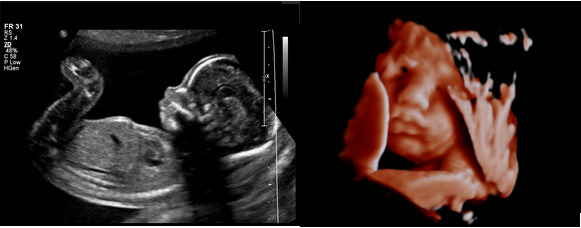

3D/4D Scans

3D/4D Baby Pictures

We offer 3D/4D scans at our Papamoa branch. They are best performed between 27-32 weeks gestation. The cost for these scans are $200. After the scan you will be sent a link to your mobile and email that will have the videos and pictures of your baby.